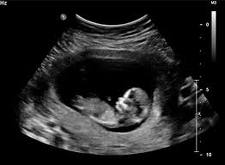

Topošajai māmiņai ir jāstājas medicīniskajā grūtniecības uzskaitē pie ārsta. Ārsts novēros mazuļa attīstību ultrasonogrāfijas izmeklējumu laikā, sekos grūtnieces asinsspiediena un asins sastāva izmaiņām - lai mazulis attīstītos normāli un dzemdībās nebūtu sarežģījumu.

Ultrasonogrāfijas pārbaude nav sāpīga un nesagādā diskomfortu.

Pēc attēla ārsts var noteikt, vai mazuļa attīstība noris normāli. Ja vecāki vēlas, var uzzināt arī gaidāmā bērniņa dzimumu.